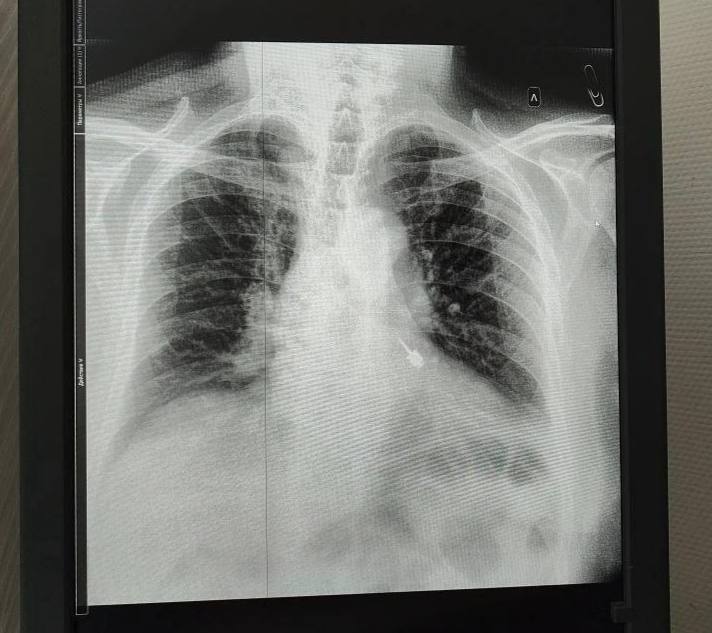

После этого он сразу поспешил в районную больницу, где врачам удалось извлечь инструмент из левого бронха.